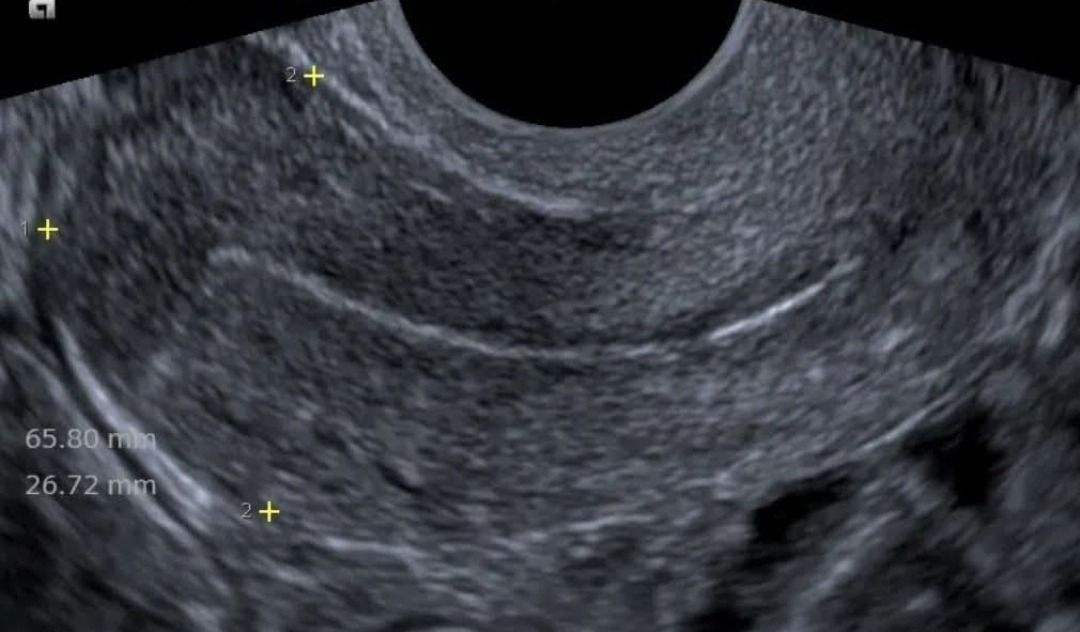

Dal 2015 al 2016 , frequenza presso U.O. Santa Maria delle Croci , Ravenna , periodo di Training di Chirurgia Laparoscopica, Endoscopica e di Isteroscopia ambulatoriale /office. In quell'anno nella stessa sede , ho  frequentato L'Ambulatorio di Diagnosi Prenatale acquisendo competenze in Ecografia Ostetrica del I-II-III trimestre.  Dopo la specializzazione ho proseguito la formazione e l'aggiornamento in particolare occupandomi dell’ Ecografia in ambito Ostetrico.

Ho acquisito "Certificate of Competence " da parte della Fetal Medicine Foundation per l'ecografia dell'11-13 settimana di gravidanza .

Da Maggio 2017 ad oggi faccio parte dello STAFF dell’Unità Operativa di Ostetricia e Ginecologia presso l’Ospedale "degli Infermi" di Faenza e dell’Ospedale "Morgagni Pierantoni "di Forli e mi occupo principalmente di Ostetricia , Gravidanza a Rischio, e dell'Ambulatorio Diagnosi Prenatale dove eseguo ecografie genetiche del I trimestre ed ecografie morfologiche e del III trimestre di gravidanza .